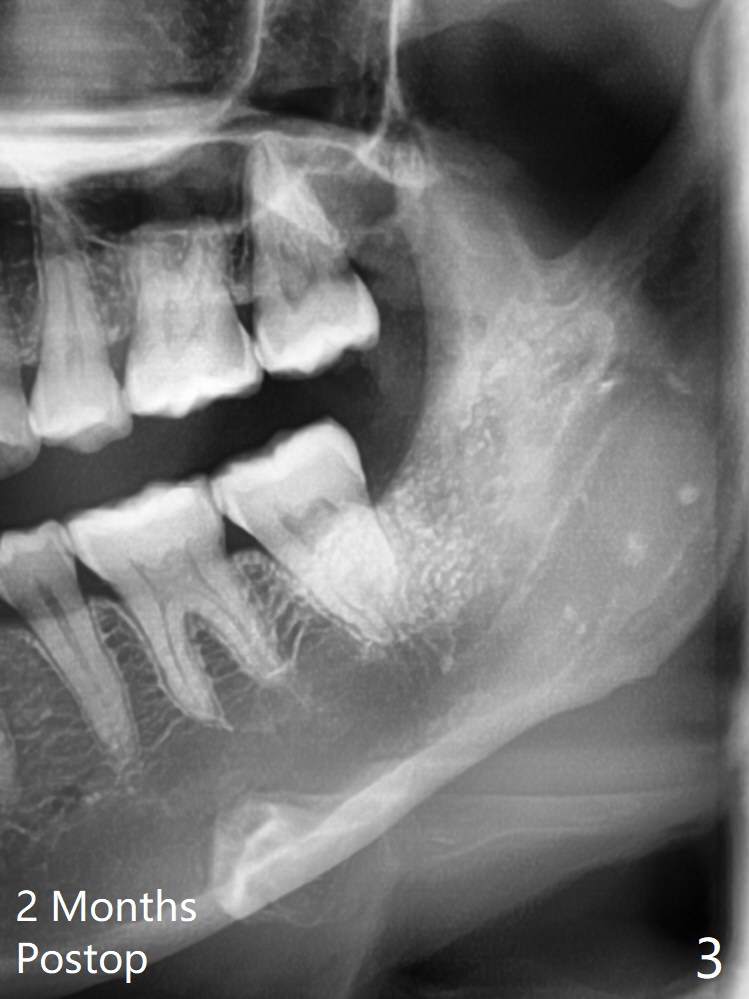

29岁(越过最佳骨再生年龄)女要求拔除左下8,它与7之间骨质非常薄(图一),拔除后需要比较好,便利的植骨材料:医用石膏(Bond Apatite,图二),表面放置1/2胶原塞,4-0 PGA缝合。术后两个月回来拔除左上8(“刺激颊粘膜”,其实远中牙龈红肿),临床上左下8近中颊侧仍有一个小开口,石膏与骨质界限开始不清楚了(图三)。